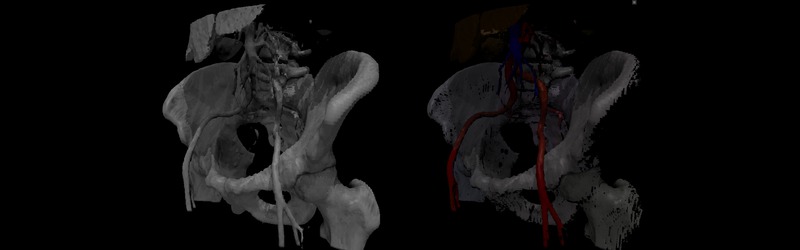

CT Abdomen

CT Head Neck

CT Wrist

MR Shoulder

MR Knee

MR Brain

MRA Brain vascular

Mouse Embryo MR

MR Angio Thorax

DPD SPECT Chest Abdomen